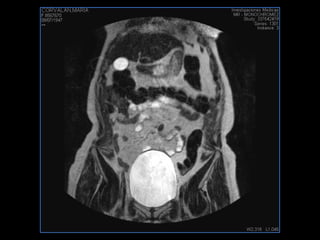

LIC ALEJANDRA GALVEZ RM DE ABDOMEN

PROTOCOLO abdomen COR T2, AXIAL supresion grasa AX T1 +SAG T2  CON   GADOLINIO :  COR T1+AX T1(DIN) SAT: NO  FASE: RL THK: 6MM  COIL:  GAP: (FACTOR 1.4) 2MM FOV: 40 CM NEX:2 SINCRONIZACION RESPIRATORIA EN 3 O 4 CICLOS ALE

resonancia de abdomen